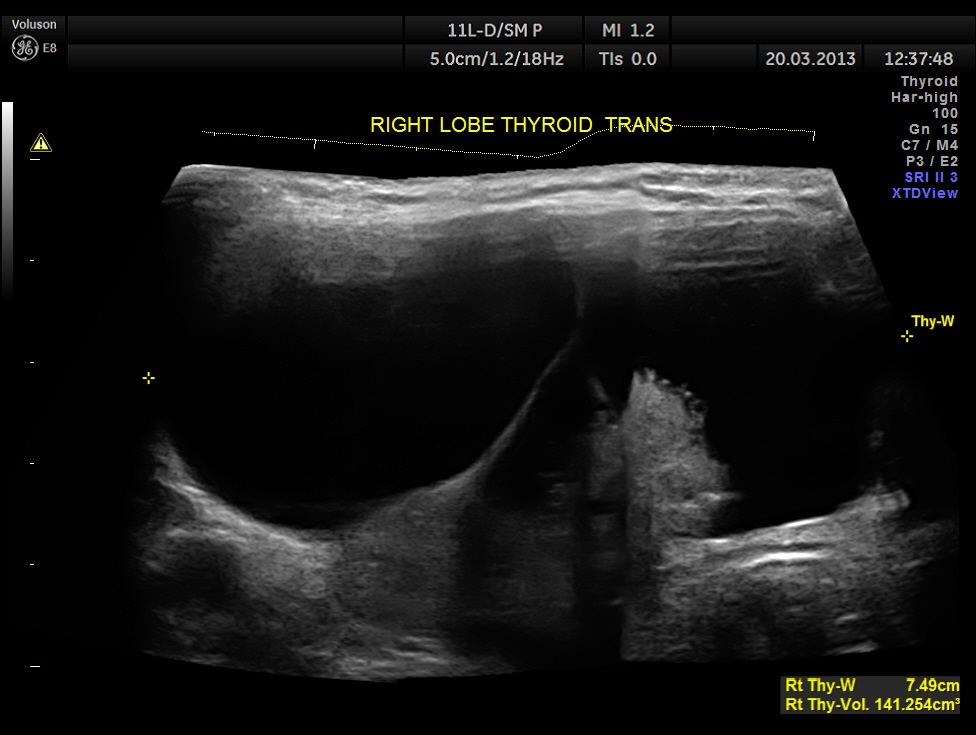

The right lobe of the thyroid was grossly enlarged , with predominantly cystic appearance , with eccentric solid tissue, with prominently increased vascularity in the solid portion.